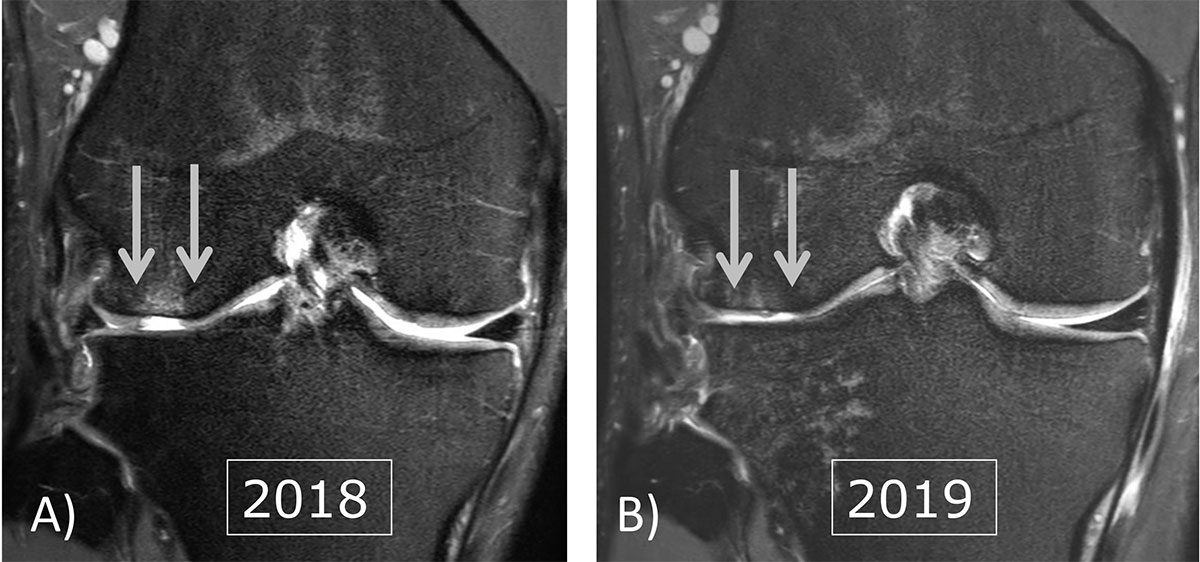

Fall 8.K.KKS.15.19.20.22 Knie Knochen und Knorpelschaden Wirbelsäulen und Gelenke Zentrum

Fall 8.K.KKS.15.19.20.22 Knie Knochen und Knorpelschaden Wirbelsäulen und Gelenke Zentrum. OP ist nötig, um das Einheilen der Knorpelzellen zu ermöglichen Grades stehen im Knorpelzentrum Wien mehrere Therapien zur Auswahl